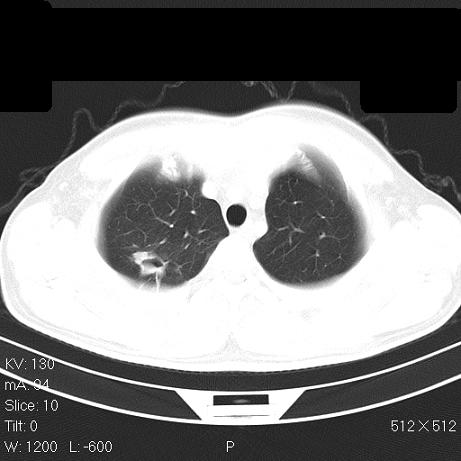

标题: CT7171B:补充治疗后2周复查

治疗后2周复查,请讨论

结合以前的ct片,还是考虑肺挫伤,吸收多了。

支持:创伤性湿肺。现肺挫裂伤(出血 积气)大部分吸收。建议继续治疗!

支持:创伤性湿肺、肺挫裂伤。现肺挫裂伤(出血、渗出、液气腔)大部分吸收。建议继续治疗!

经治疗后病灶明显吸收,考虑创伤性湿肺、肺挫裂伤